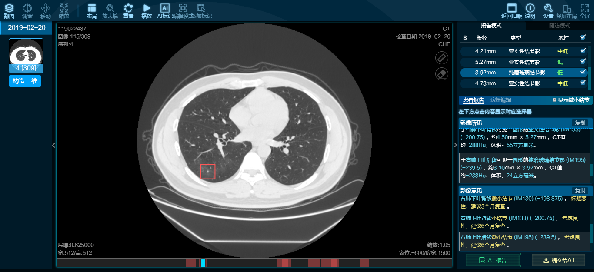

AI赋能,高效诊断

该技术基于人工智能的肺结节自动检测,采用深度卷积神经网络算法自动检测CT图像的肺结节,辅助医生大大提高诊断的正确率。

图片